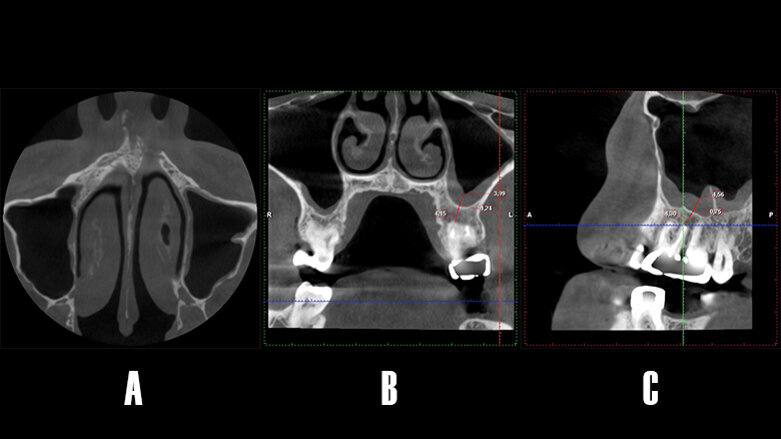

La TCHC muestra una imagen osteolítica menos radiodensa que afecta la región apical de 2.6, esta lesión compatible con un proceso osteolítico, es visible en los planos axial, coronal y sagital. Además, se observa cómo el seno maxilar izquierdo, relacionado al diente afectado, se torna más radiodenso y totalmente ocupado (Fig. 3).

Figura 3. Tomografía de haz cónico. A) Corte en el plano axial: se puede observar un área poco radiodensa en la raíz palatina de 26, y advierte la presencia de un proceso osteolítico de origen endodóntico. B) Corte coronal: se observa cómo el patrón de la lesión se extiende en sentido vestíbulo-palatino, además, se aprecia la cavidad sinusal anexa al diente afecto muy radiodensa respecto a su par contralateral. D) Corte sagital: se aprecia la opacificación completa del seno maxilar, la presencia de una septo óseo. La lesión apical tiene una mayor dimensión en la raíz palatina de 26.